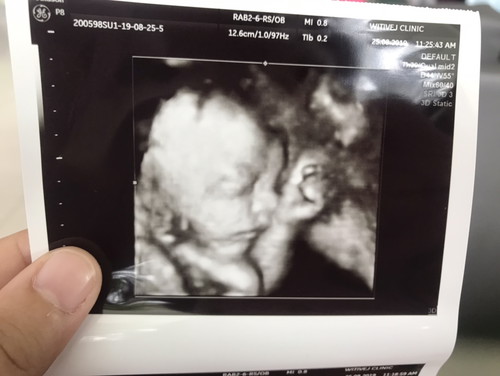

พึ่งจะ26+3. แต่ลูกหมู น้ำหนักเท่าเด็ก27สัปดาห์ไปแล้วค่ะ ?